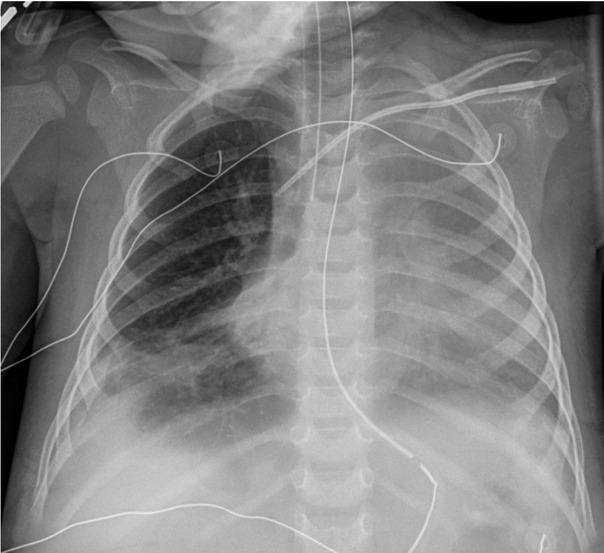

The patient was given a trial of a ketogenic diet (KD) which did not result in an elevation of lactate levels (Figure 2). He remained on prolonged mechanical ventilation secondary to the development of acute respiratory distress syndrome (ARDS). On the thirteenth day of hospitalisation, he developed severe ARDS with an oxygenation index of 32.7. His chest radiograph, after the development of ARDS, is shown in Figure 3. He also required inhaled nitric oxide, oscillator and prone positioning during his ICU stay. On the thirty-eighth day of hospitalisation he was extubated and subsequently transferred out of the PICU to the general inpatient paediatrics service for further management.

Fig. 3

Chest radiograph on hospital day 13. The image shows generalized opacification of the left hemithorax with no mediastinal shift. This could represent a combination of pleural fluid and atelectasis. Persistent right lower lobe atelectasis is seen along with right pleural fluid.